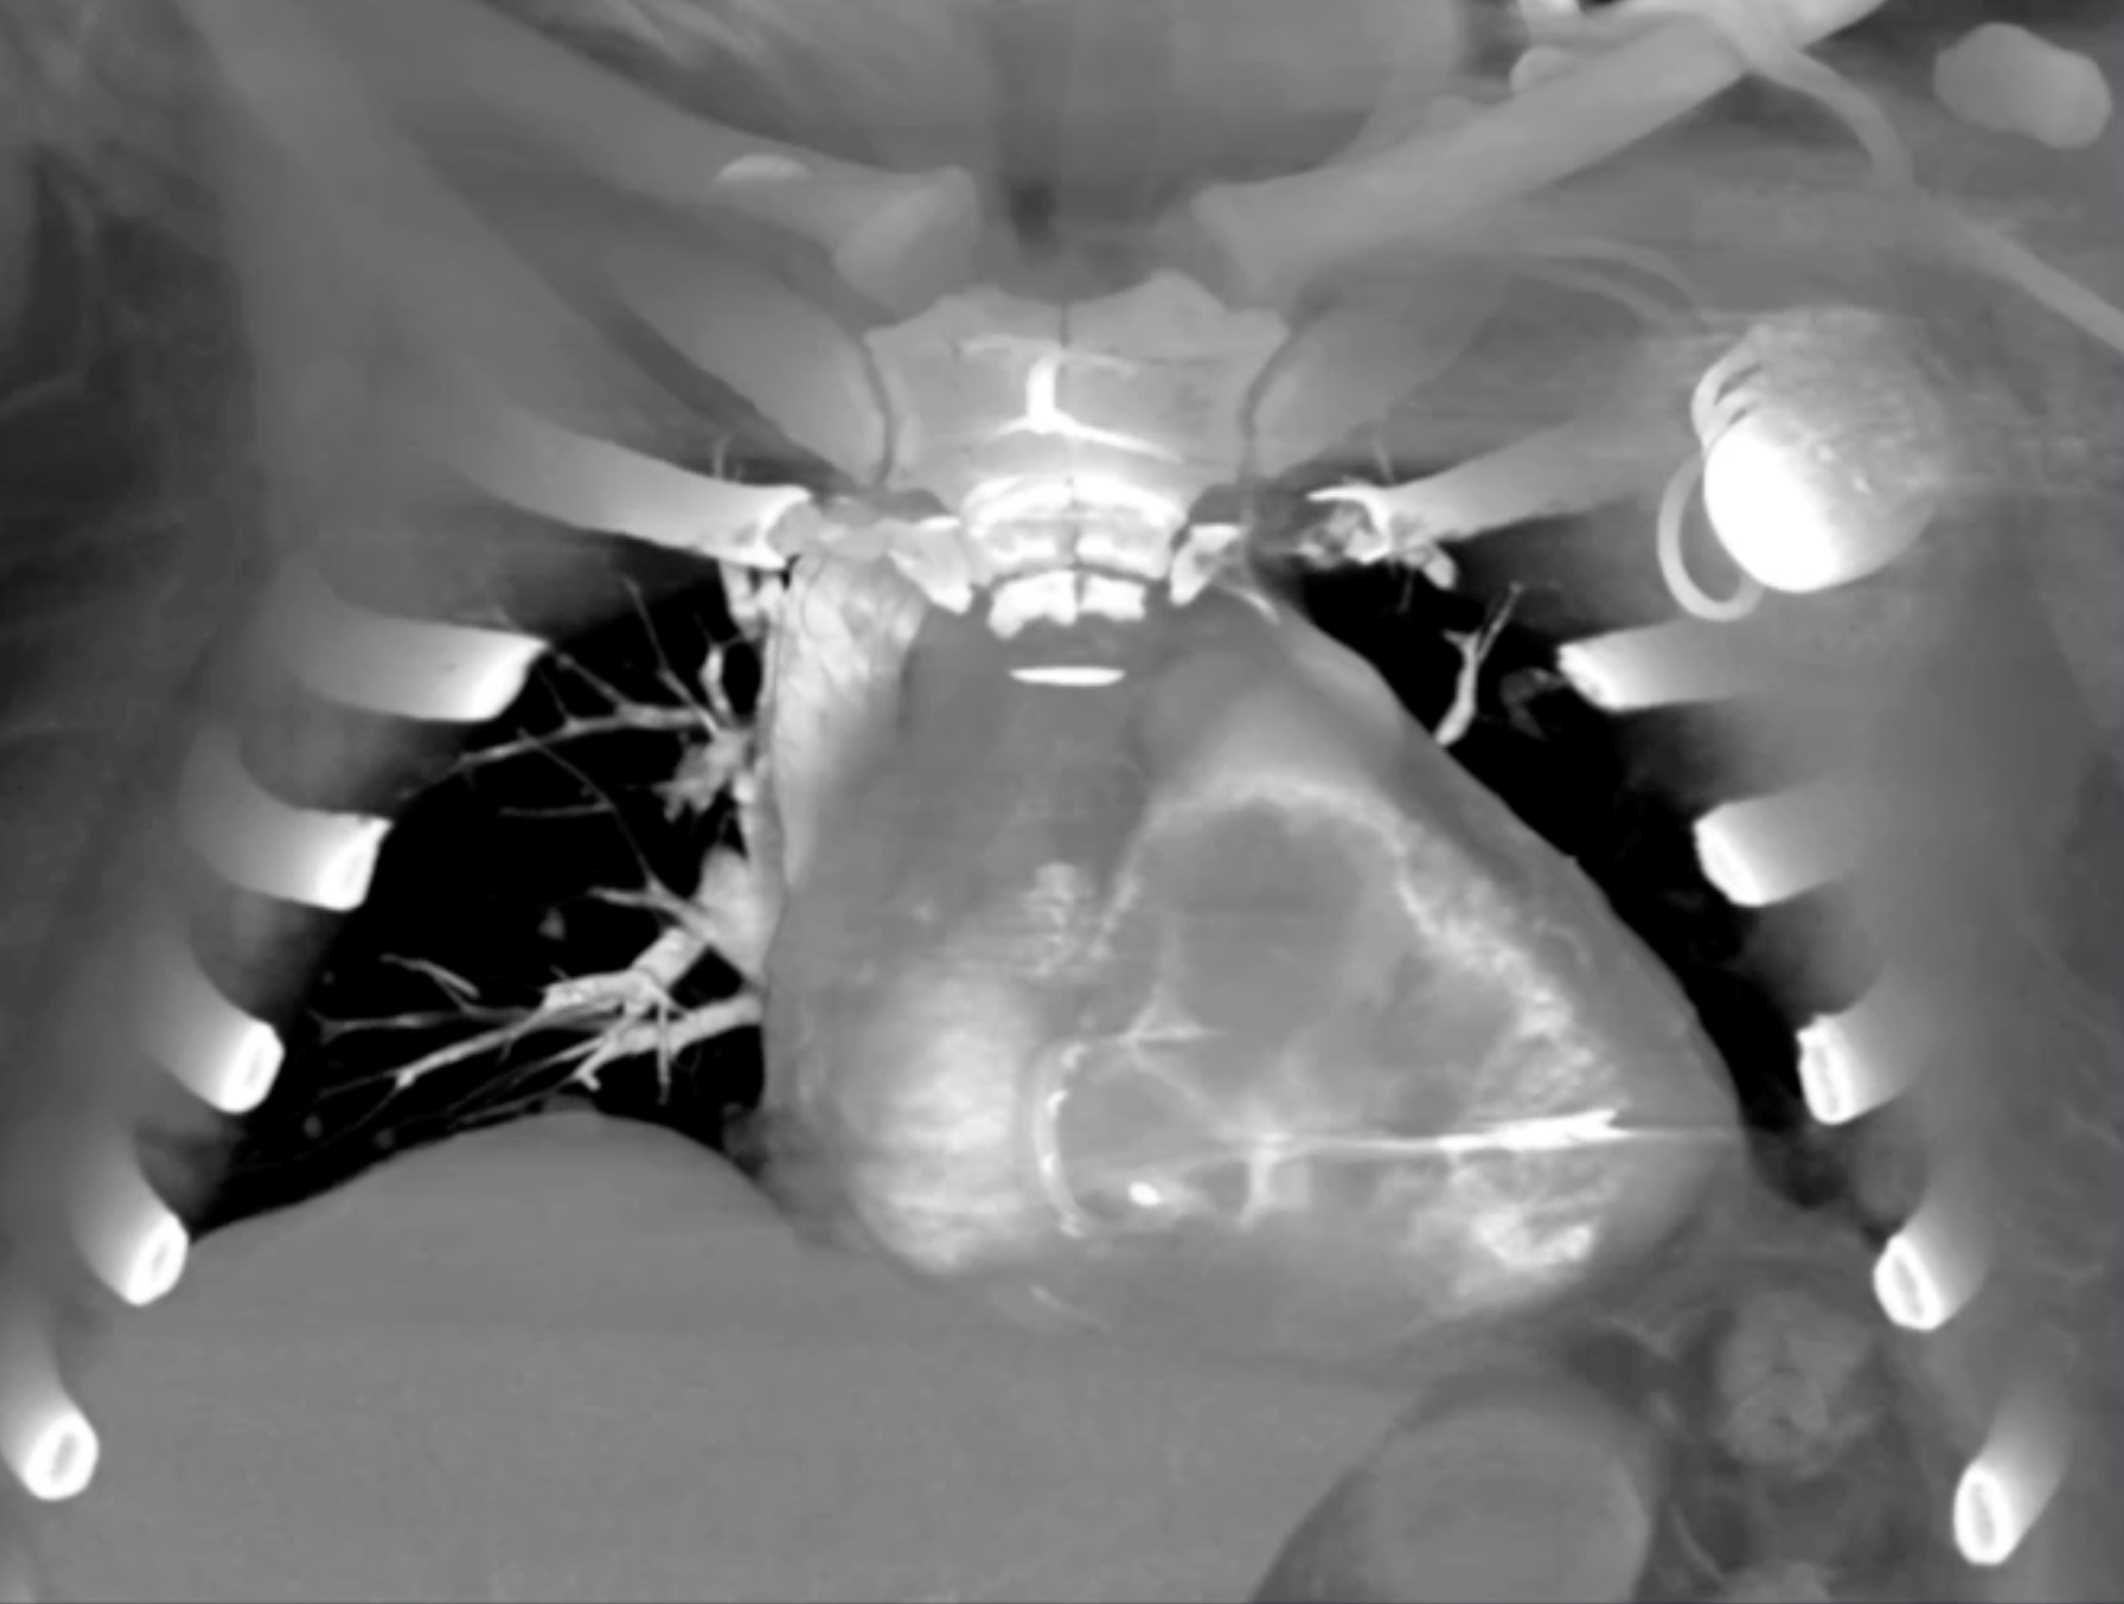

Primary Spindle Cell Carcinoma of the Right Ventricle